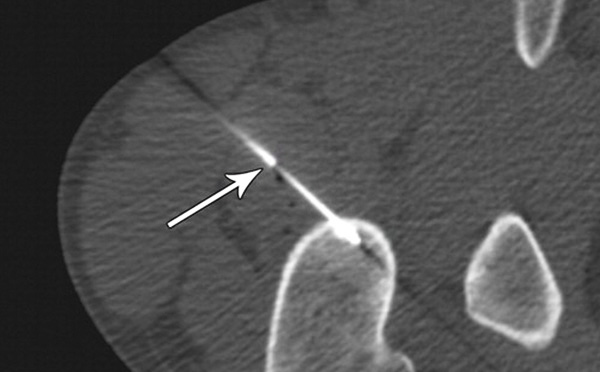

Osteoid Osteoma

Laser ablation is proved to be best treatment for Osteoid osteoma, a painful Bone tumor.

This is a Non Malignant Bone Tumor which can be totally cured by LASER Treatment. Osteoid Osteoma is a rare bone tumor which presents...